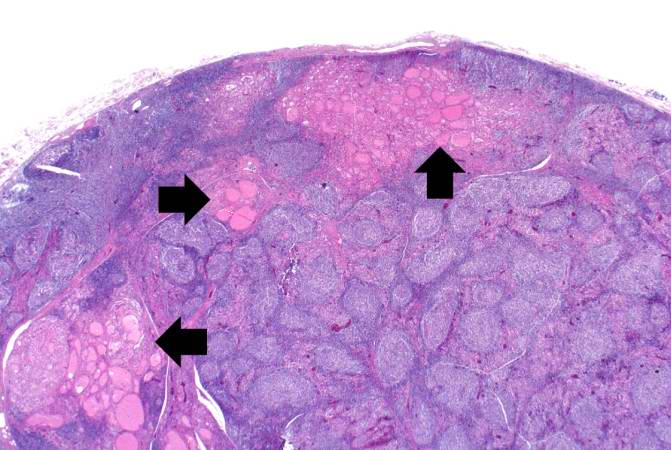

Лечение тиреоидита Хашимото: препараты и схемы